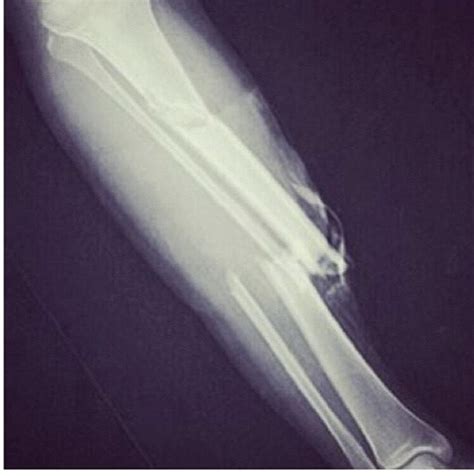

These injuries can occur due to sudden changes in direction, collisions with other players, or falls. The basketball injury Kevin Ware experienced was particularly shocking because it involved a compound fracture of his right leg, which is a severe and visually disturbing injury.

The basketball injury Kevin Ware suffered during the 2013 NCAA Tournament was a pivotal moment in sports history. On March 31, 2013, during a regional final game between the Louisville Cardinals and the Duke Blue Devils, Ware landed awkwardly after attempting to block a shot. The impact caused his right leg to snap, resulting in a compound fracture. The injury was so severe that the bone protruded through the skin, a sight that sent shockwaves through the arena and viewers at home.